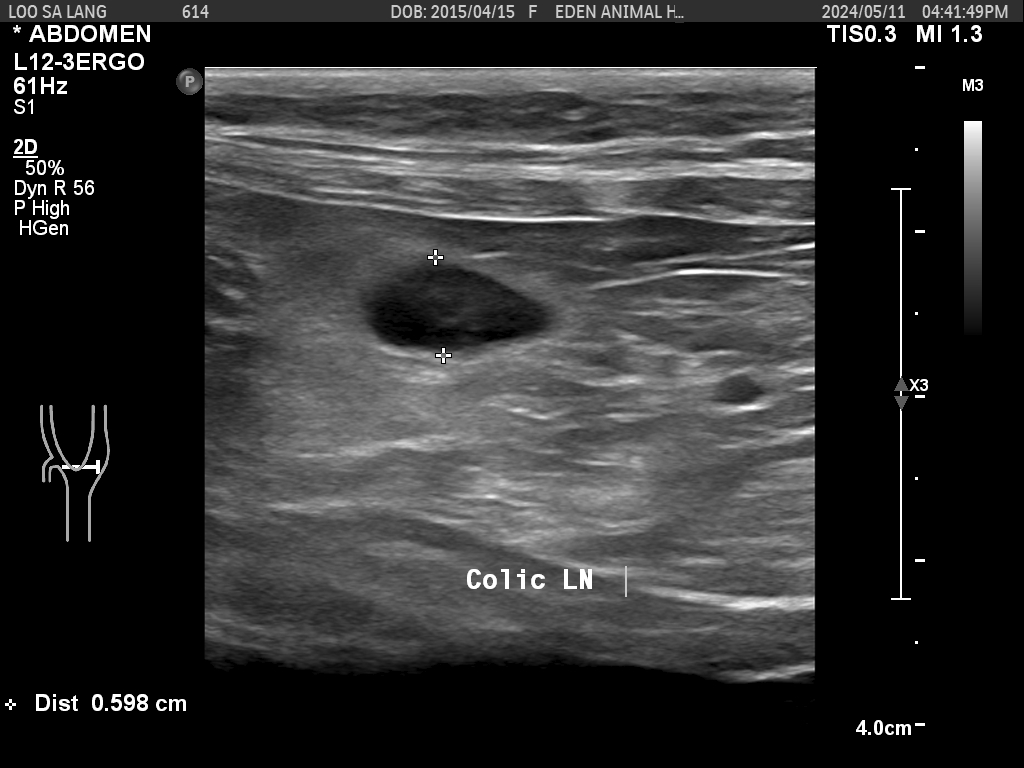

정밀복부초음파를 진행했다.

근데 림프절이 건강검진 때보다 부어 있었다.

그래서 2주 동안 약을 복용 후

다시 내원해서 검사를 해보기로 했고

그때 결과에 따라 진행을 하기로 했다.